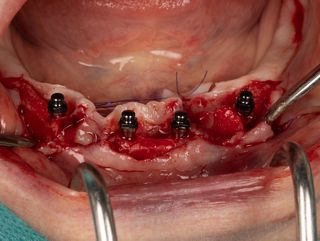

3c. Two mini-implants with a diameter of 2.6 mm and a length of 12 mm were placed in positions 32 and 42, first manually and then using a contra-angle. The insertion torque recorded at the end of the procedure was 21 N.cm in 32 and 17 N.cm in 42. The implants were positioned 0.5 mm subcrestal, i.e. with slight burial of the smooth neck.

3c

3d

3d. Two mini-implants with a diameter of 2.6 mm and a length of 12 mm were placed in positions 34 and 44 using the same protocol as for the previous mini-implants. The torque obtained was 27 Ncm in 34 and 37 Ncm in 44.